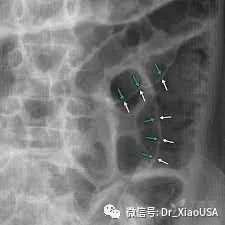

12.食道破裂典型CT表现是什么?

a) 颈部皮下积气

b) 胸部皮下积气

c) Naclerio V型征

d) 主动脉旁气体

e) 纵隔气肿

13.胃肠道穿孔常见症状是什么?